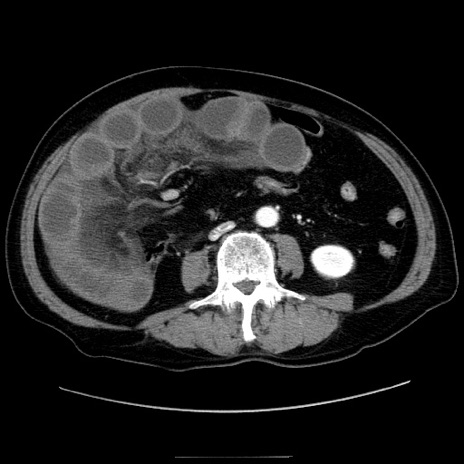

冠状断像

【症例】80歳代男性

【主訴】臍周囲痛

【現病歴】約6時間前から臍下部痛が出現。次第に腹部膨隆・背部痛も生じてきたため来院。背部痛の場所は変化しない。

【身体所見】意識清明、BT 36.3℃、BP  131/87mmHg、P 87bpm、SpO2 100%(RA)、臍周囲自発痛・圧痛あり、反跳痛なし、自発痛部位に一致して板状硬あり、腹部膨隆、腸雑音減弱、CVA tenderness両側陰性。

【データ】WBC 19600、CRP 0.33